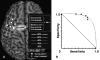

Methods: Fourteen children with intractable neocortical epilepsy (age: 1-16 years) who had subsequent resective surgery were retrospectively studied. The subjects underwent a high-resolution MRI and prolonged subdural EEG recording. Spectral analysis was applied to 3 habitual focal seizures. After fast Fourier transformation of the EEG epoch at ictal onset, an amplitude spectral curve (square root of the power spectral curve) was created for each electrode. The EEG magnitude of ictal rhythmic discharges was defined as the area under the amplitude spectral curve within a preset frequency band including the ictal discharge frequency, and calculated for each electrode. The topography mapping of ictal EEG magnitude was subsequently displayed on a surface-rendered MRI. Finally, receiver operating characteristic (ROC) analysis was performed to evaluate the consistency between quantitatively and visually defined ictal onset zones.

Results: The electrode showing the maximum of the averaged ictal EEG magnitude was part of the visually defined ictal onset zone in all cases. ROC analyses demonstrated that electrodes showing >30% of the maximum of the averaged ictal EEG magnitude had a specificity of 0.90 and a sensitivity of 0.74 for the concordance with visually defined ictal onset zones.